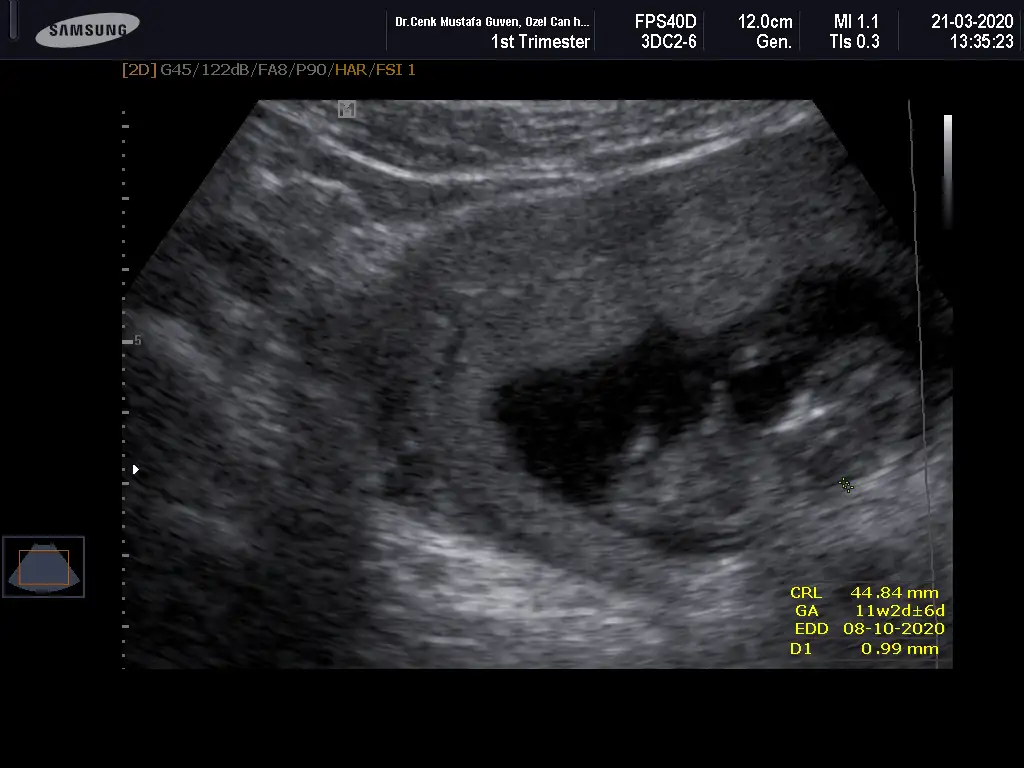

Merhabalar, ctesi ikili test icin gittim 11+6 idim. Suana kadar hep haftayla uyumlu giderdi sat. Ama bu sefer 12+6 cıktım. Yine de cinsiyet yorumlar mısınız? Gec mi kaldım? Bir de doktor tahminini söyledi ama emin değil. Kafanız karışmasın diye en son söyleyeceğim.

Eklentiler

Bir de bunu verdi doktor. Sanırım bacak arası ve kenardakiler de bacakları burada. 11+6 idim.